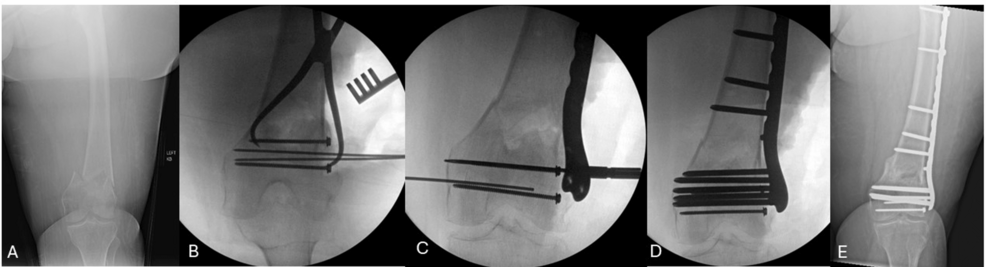

Distal Femur Fractures: Push Screw Reduction Technique